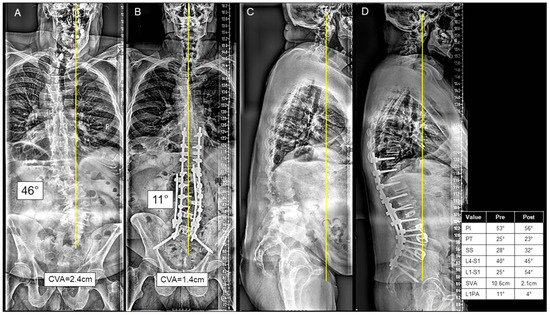

For the P-only group, the posterior approach included lumbar interbodies in 36 (17.6%) patients. These were most commonly L4-L5 (36.1%), L5-S1 (58.3%), L3-L4 (25.0%), and L2-L3 (11.1%). The majority of P-only cases were performed in one anesthetic setting. A three-column osteotomy was performed in 34 (16.7%) cases. A thoracolumbar UIV to sacrum/pelvis fusion was performed in 58 (28.4%) cases, and an upper/middle thoracic to sacrum/pelvis fusion was performed in 103 (50.4%) cases. A representative P-only case is presented in Figure 4A–D.

Figure 4.

(A–D) A case presentation of a 67-year-old male with severe L2 and L3 right-sided radiculopathy, left-sided L4 radiculopathy, severe mechanical back pain, and inability to walk for more than 5–10 min, who was found to have a significant degenerative scoliosis in the thoracolumbar and lumbar spine on the postero-anterior (PA) (A) and lateral X-rays (C). The patient underwent a posterior-only approach consisting of T10-ilium posterior spinal instrumentation; T10-S1 inferior facetectomies; L1-S1 posterior column osteotomies; a total of 3 transforaminal lumbar interbody fusions at L3/L4, L4/L5, L5/S1; decompressive foraminotomies at L5/S1, L4/L5, L3/L4 and L2/L3; and a cobalt kickstand rod from T11/12-S1 with compression and distraction forces to correct the scoliosis, as seen on the postoperative PA (B) and lateral X-rays (D). The patient was discharged home at postoperative day 5.